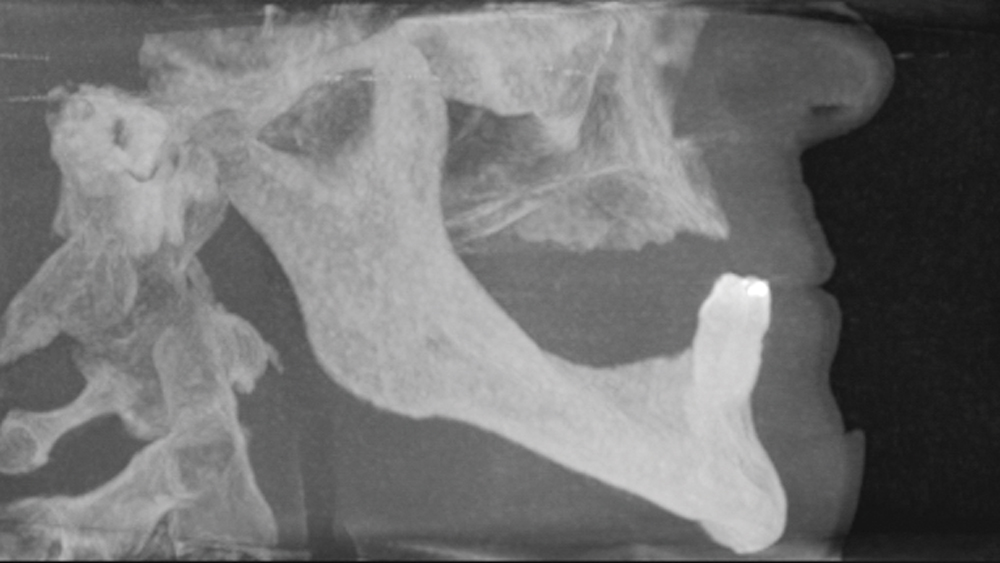

By comprehensively assessing the patient’s chief complaint, bone volume, anatomical landmarks, and the fit, stability and comfort of any existing oral appliances, clinicians can confidently determine whether a traditional complete denture or an implant-supported prosthesis is indicated. After presenting the treatment options, doctors can work with the patient in developing a solution that is both affordable and effective.

This patient was unhappy with the esthetics of her existing upper denture as well as the discomfort and instability caused by her loose-fitting mandibular partial denture. Although her concerns with the maxillary denture could be addressed with a new, more esthetic appliance, she preferred implant treatment for her mandible, where a fixed solution was needed to adequately restore function, stability and comfort.

Treatment plan:

The patient’s remaining mandibular teeth were extracted followed by immediate implant placement and delivery of a fixed provisional appliance. After integration of the implants, the prosthetic designs for the new upper denture and lower implant restoration were determined in tandem. Ultimately, the dual-arch restorations addressed the functional and esthetic challenges of the case while staying within the financial means of the patient, demonstrating the benefits of a flexible, multifaceted approach to restorative dentistry.